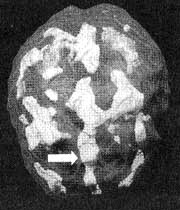

Мозг Роба. Результаты сканирования SPECT

Трехмерное изображение — активный мозг, вид сверху.

До лечения: обратите внимание на выраженное усиление активности в поясной системе (см. стрелку).

После лечение Anafranil. Активность поясной системы нормализовалась.